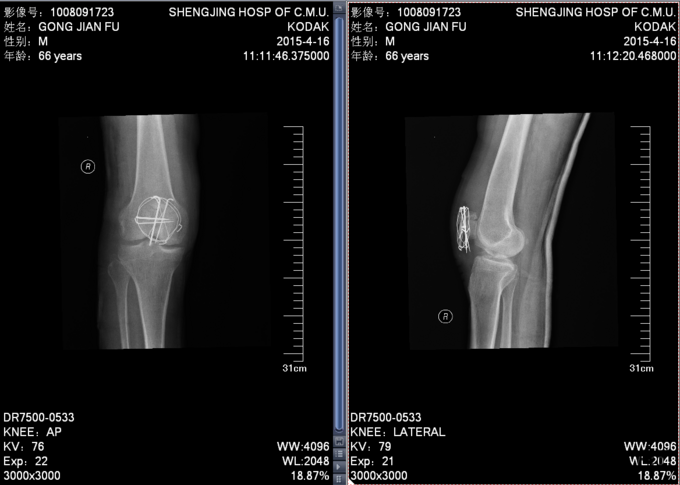

诊断:右侧髌骨骨折,治疗:于麻醉下行髌骨骨折切开复位内固定术

术后给予患者抗炎之疼消肿等对症治疗,术后第二天给予患者患肢CPM功能锻炼